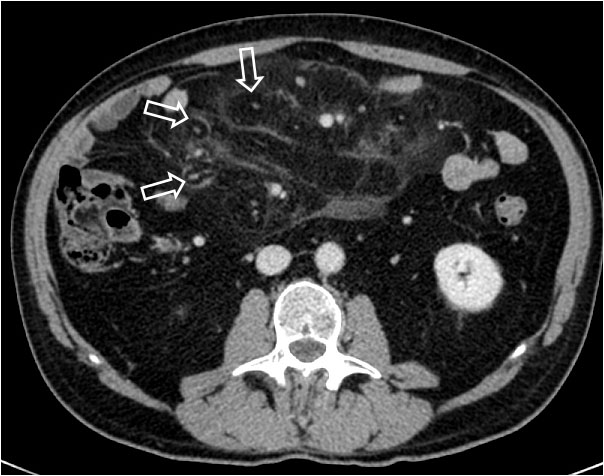

La presencia de un halo graso alrededor de los vasos mesentéricos, visto en TC, fue inicialmente descrito en la mesenteritis esclerosante aunque posteriormente se ha demostrado que no es específico ya que puede estar presente en el linfoma de Hodgkin tratado con quimioterapia.

La imagen muestra un aumento de la densidad del mesenterio que respeta las zonas que rodean a los vasos produciendo esa imagen de anillos grasos.

El artículo de referenciA es de C. valls: Fat-ring sign in sclerosing mesenteritis. AJR 2000; 174:259-260. En: http://www.ajronline.org/doi/full/10.2214/ajr.174.1.1740259.